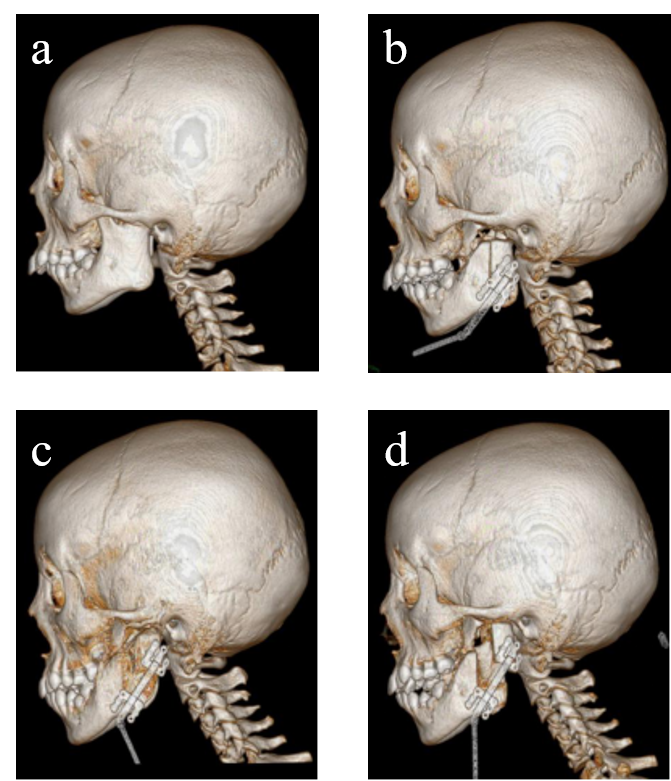

Figure 4. Simultaneously surgical correction of the oblique jaw following unilateral temporomandibular joint ankylosis by transport distraction osteogenesis. a: preoperative lateral CT image. b: postoperative lateral CT image. c: CT image at the end of distraction. d: CT image at the end of consolidation.